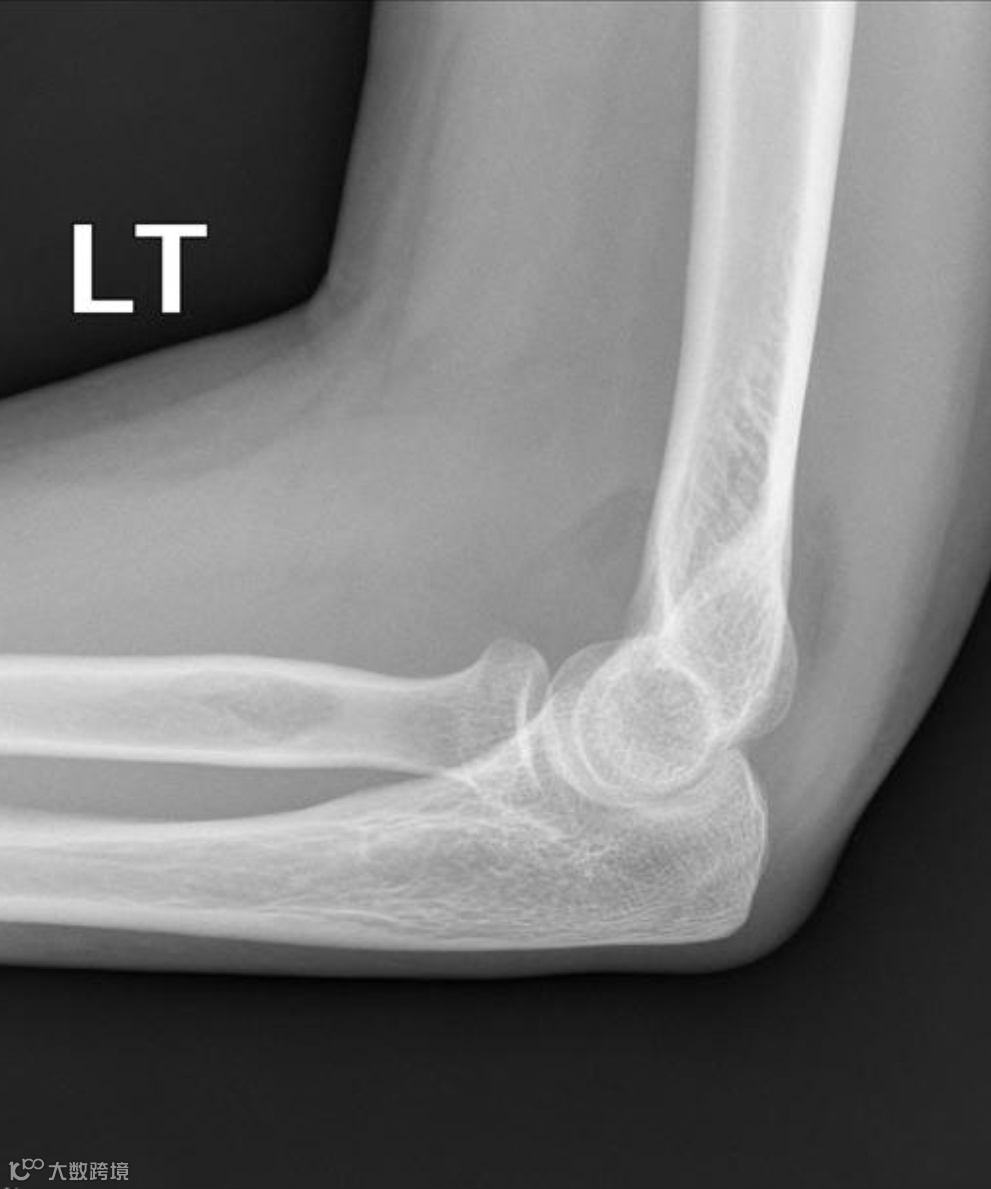

在正常的肘关节侧位X光片上:

前脂肪垫:有时可以隐约看到,表现为紧贴骨骼的一条细线状或窄三角形低密度阴影。

后方脂肪垫:因为深埋在鹰嘴窝里,正常情况下在X光片上是看不见的。

正常肘关节X线侧位,前脂肪垫(红色箭头)为紧贴肱骨的一条细线状或窄三角形低密度影,后脂肪垫(黄色箭头)看不见。